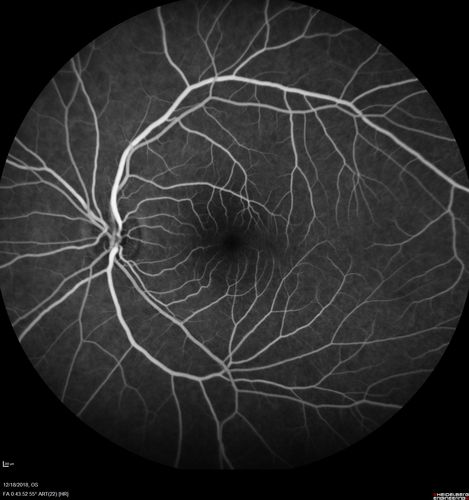

White Retinal Artiole Left eye - Inferotemporal

31 year old female with migraines and headaches for the last 12-13 years. Sometimes she gets the visual symptoms with the migraine. When she gets the migraines the pain is on the left side of her head. She gets the problem a few times a month, sometimes more. They usually last 5-6 hours. She has not had a permanent vision change. When she gets a vision change there are spotty dots of blue neon lights in her vision. With her glasses her two eyes are about the same. VA 20/16 in Each Eye